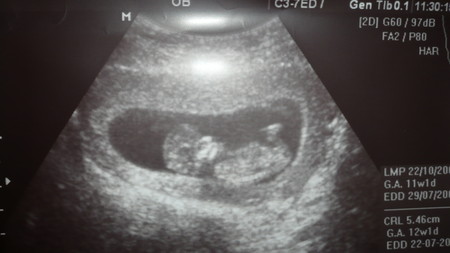

Ура-а-а! Сегодня я видела свою малышку ( правда пол мне все таки не сказали рано еще 11,1 всего)- но все равно называю малышкой ( хотя никто не исключает и мальчика)

Какое это счастье! я первый раз делала УЗИ в 5 нед - там просто плодное яйцо и все - а тут "живой и здоровенький человечек" с пульсом 162 уд/мин и размером 5 см 46 мм. Никаких отклонений от нормы - и толщина шейной складки и остальное все соответсвует. Растет опережая свое развитие ( акушерский срок мне поставили чуть ли не 12,1 нед). Ручонками машет, сердечко стучит - я прям прослезилась на УЗИ. Правда все таки немного расстроилась что одна - мне тут муж все говорил двойня будет - однозначно - в роду и у меня и у него были близняшки. Ну я и настроилась - а тут одна. Но все равно кем ты не была Девочкой или Мальчиком - я тебя очень очень люблю и жду.

Ниже прикладываю фото. Правда прошу прощение за качество - я фотографировала фотографию- сканера нет.